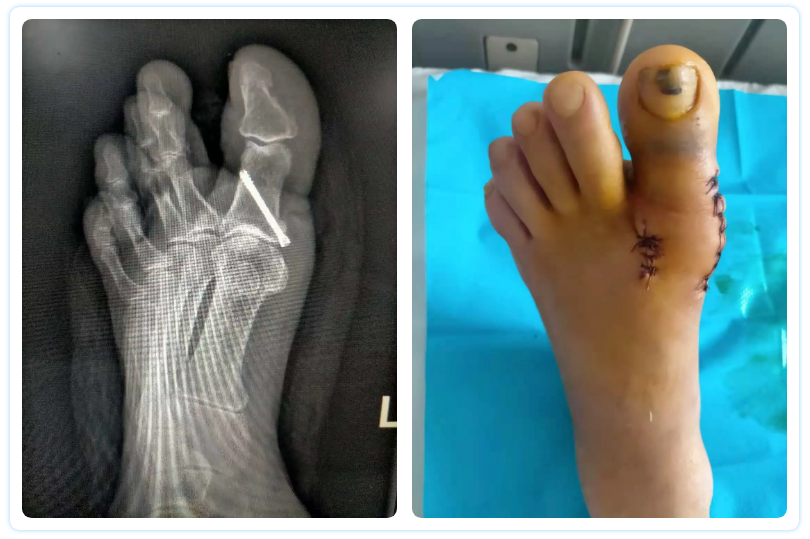

李大娘左腳拇趾30年前出現(xiàn)外翻情況,由于不影響生活,李大娘就沒多在意,但日積月累前足明顯增寬,在一年前疼痛加重,持續(xù)加重的疼痛感已使李大娘無法正常行走,嚴(yán)重影響日常生活。家人聽說北大醫(yī)療淄博醫(yī)院骨外科有專門學(xué)習(xí)拇外翻治療的醫(yī)生,于是求診于北大醫(yī)療淄博醫(yī)院。骨外科副主任醫(yī)師李然醫(yī)生接診了李大娘,對其進(jìn)行體格檢查,結(jié)合CT結(jié)果后,判斷為左足拇趾外翻畸形,李然醫(yī)生認(rèn)真分析研究了李大娘的病情,骨科團(tuán)隊(duì)進(jìn)行了縝密的術(shù)前討論,對手術(shù)方案及圍手術(shù)期處理進(jìn)行詳細(xì)預(yù)案,并在與患者與家屬進(jìn)行充分溝通后,決定實(shí)施拇外翻矯形術(shù)。

經(jīng)過完善的術(shù)前準(zhǔn)備,在硬膜外麻醉下,李然醫(yī)生與副主任醫(yī)師段偉醫(yī)生相互配合,對外側(cè)軟組織松解、內(nèi)側(cè)骨贅切除,Akin截骨術(shù)。整個(gè)手術(shù)過程精細(xì)、嚴(yán)謹(jǐn)而又自然有序,從麻醉開始到患者被送出手術(shù)室,整個(gè)手術(shù)在30分鐘內(nèi)順利完成。術(shù)后,拇外翻畸形得到矯正,疼痛得到緩解,經(jīng)過骨科護(hù)理團(tuán)隊(duì)的精心呵護(hù),術(shù)后第二天可以下地活動(dòng)。李大娘也對手術(shù)效果相當(dāng)滿意。目前李大娘已康復(fù)出院。